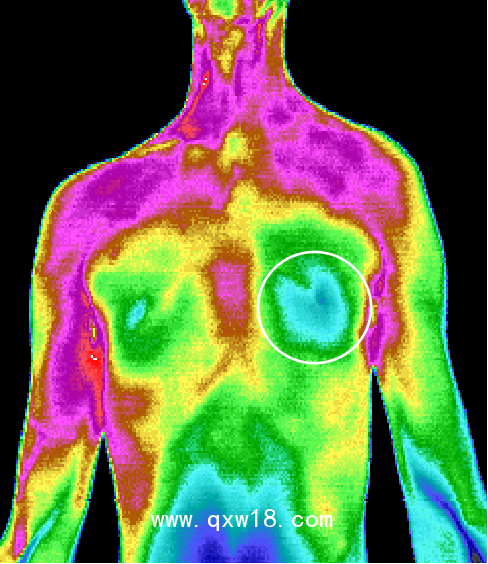

中醫(yī)熱CT是醫(yī)學(xué)技術(shù)和紅外攝像技術(shù)、計(jì)算機(jī)多媒體技術(shù)結(jié)合的產(chǎn)物,人體是一個(gè)天然的生物發(fā)熱體,由于解部結(jié)構(gòu)、組織代謝、血液循環(huán)及神經(jīng)狀態(tài)的不同,機(jī)體各部位溫度不同,形成不同的熱場(chǎng),中醫(yī)熱CT被動(dòng)接收人體組織細(xì)胞代謝熱源,可以反映出人體局部0.05°C~0.1°C的溫度微弱變化,0介入、0損傷、0輻射、0痛苦,結(jié)合Al智能分析可將傳統(tǒng)中醫(yī)通過“四診八綱”等原始手段獲取的人體信息,通過數(shù)值化和可視化的彩色圖像,形象客觀的呈現(xiàn)出來觀測(cè)臟腑的寒熱狀態(tài)、經(jīng)絡(luò)氣血流通情況、中醫(yī)藥效果的可視化觀察,針灸,推拿按摩,刮癡拔罐等治療的指導(dǎo)及效判定、參與九種體質(zhì)的評(píng)測(cè),拓展了中醫(yī)四診,增加了中醫(yī)的“第五種診斷方法”,推動(dòng)中醫(yī)現(xiàn)代化的發(fā)展,被形象的比喻成“扁鵲之眼”

???中醫(yī)熱CT檢測(cè)最重要的一個(gè)優(yōu)勢(shì)就是早期預(yù)警,X光、B超、CT等檢測(cè)技術(shù)都屬于結(jié)構(gòu)影像技術(shù),只有在疾病形成病灶之后才能發(fā)現(xiàn)疾病。而疾病在出現(xiàn)組織結(jié)構(gòu)和形態(tài)變化之前,細(xì)胞代謝就會(huì)發(fā)生異常。中醫(yī)熱CT可以反映出人體后部0.05°C~0.1C的溫度微弱變化,因此能更早地發(fā)現(xiàn)問題。檢測(cè)所得為高清晰度彩色圖像,具有更直觀、更形象的特點(diǎn),結(jié)合AI智能分析,所得結(jié)果精準(zhǔn)度更高,成為了目前我們認(rèn)知亞健康最有力的測(cè)評(píng)技術(shù)。

紅外熱CT檢測(cè)最重要的一個(gè)優(yōu)勢(shì)就是早期預(yù)警。X光、B超、CT等檢測(cè)技術(shù)它們都屬于結(jié)構(gòu)影像技術(shù),只有在疾病形成病灶之后才能發(fā)現(xiàn)疾病。而疾病在出現(xiàn)組織結(jié)構(gòu)和形態(tài)變化之前,細(xì)胞代謝就會(huì)發(fā)生異常。醫(yī)用紅外熱CT可以反映出人體局部0.05°C ~ 0.1°C的溫度微弱變化,因此能更早地發(fā)現(xiàn)問題。檢測(cè)所得為高清晰度彩色圖像,具有更 直觀、更形象的特點(diǎn),結(jié)合ai智能分析,所得結(jié)果精準(zhǔn)度更高,成為了目前我們認(rèn)知亞健康最有力的測(cè)評(píng)技術(shù)。紅外熱CT彌補(bǔ)了其他醫(yī)用影像設(shè)備的不足,并能很好地進(jìn)行影像互補(bǔ)。

6、適用廣泛:適用于臨床內(nèi)科、外科、婦科,兒科等所有科室。 可以對(duì)全身九大系統(tǒng)、上百種疾病有很好輔助診斷作用,特別是對(duì)心腦血管,乳腺,甲狀腺疾病 以及惡性腫瘤的早期發(fā)現(xiàn)有重大的參考價(jià)值。